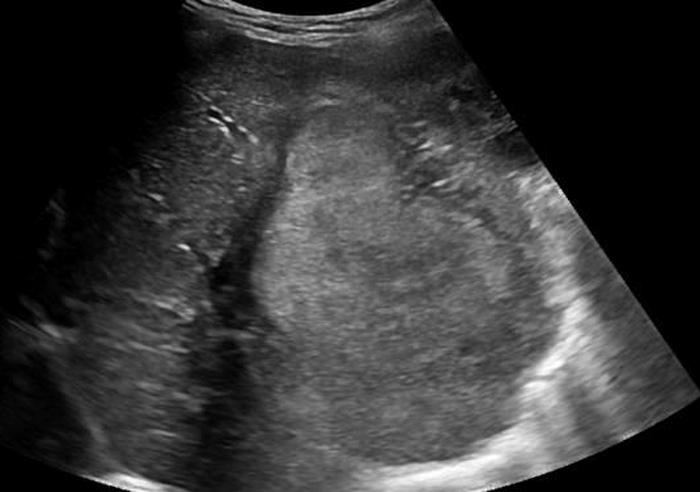

Liver mets from ?

Metastasis to the liver

colon

Most common

Liver mets from ?

Metastasis to the liver

Breast

Liver mets from ?

Metastasis to the liver

Lung

Liver mets from ?

Lymphoma